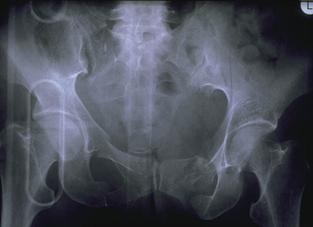

Fractura de bazin

. Radiografie in incidenta AP Fractura de spina

iliaca antero-superioara

Dupa aplicarea benzii de stabilizare Dallas prin avulsie. - Stabila -

Fractura de ram pubian cu minima

deplasare Fractura transversa de

sacru sau coccis

- Stabila - - Stabila -